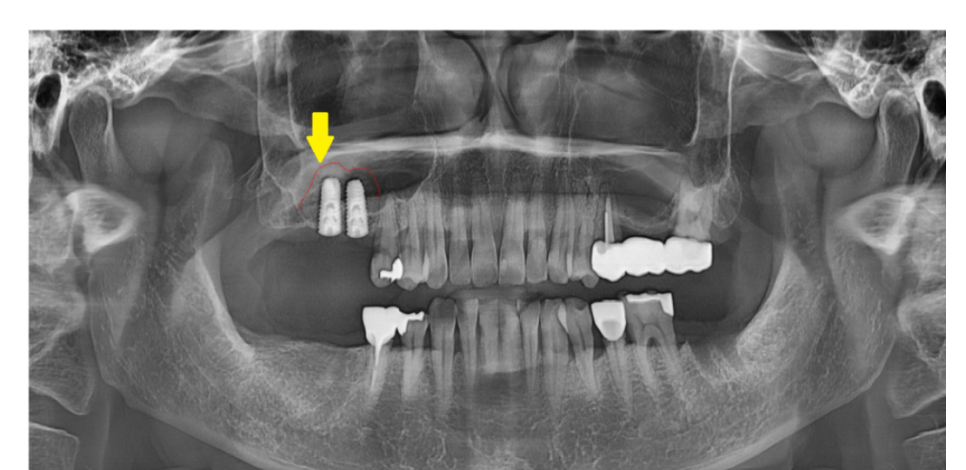

혈관이 파열되어 코피가 생길 수 있습니다.

수술 중 작은 혈관이 파열되었다거나

수술 후 주의사항을 지키지 않아

상악동 내부 압력이 높아지면서 출혈이 발생할 수 있습니다.

240521 거상된 상악동